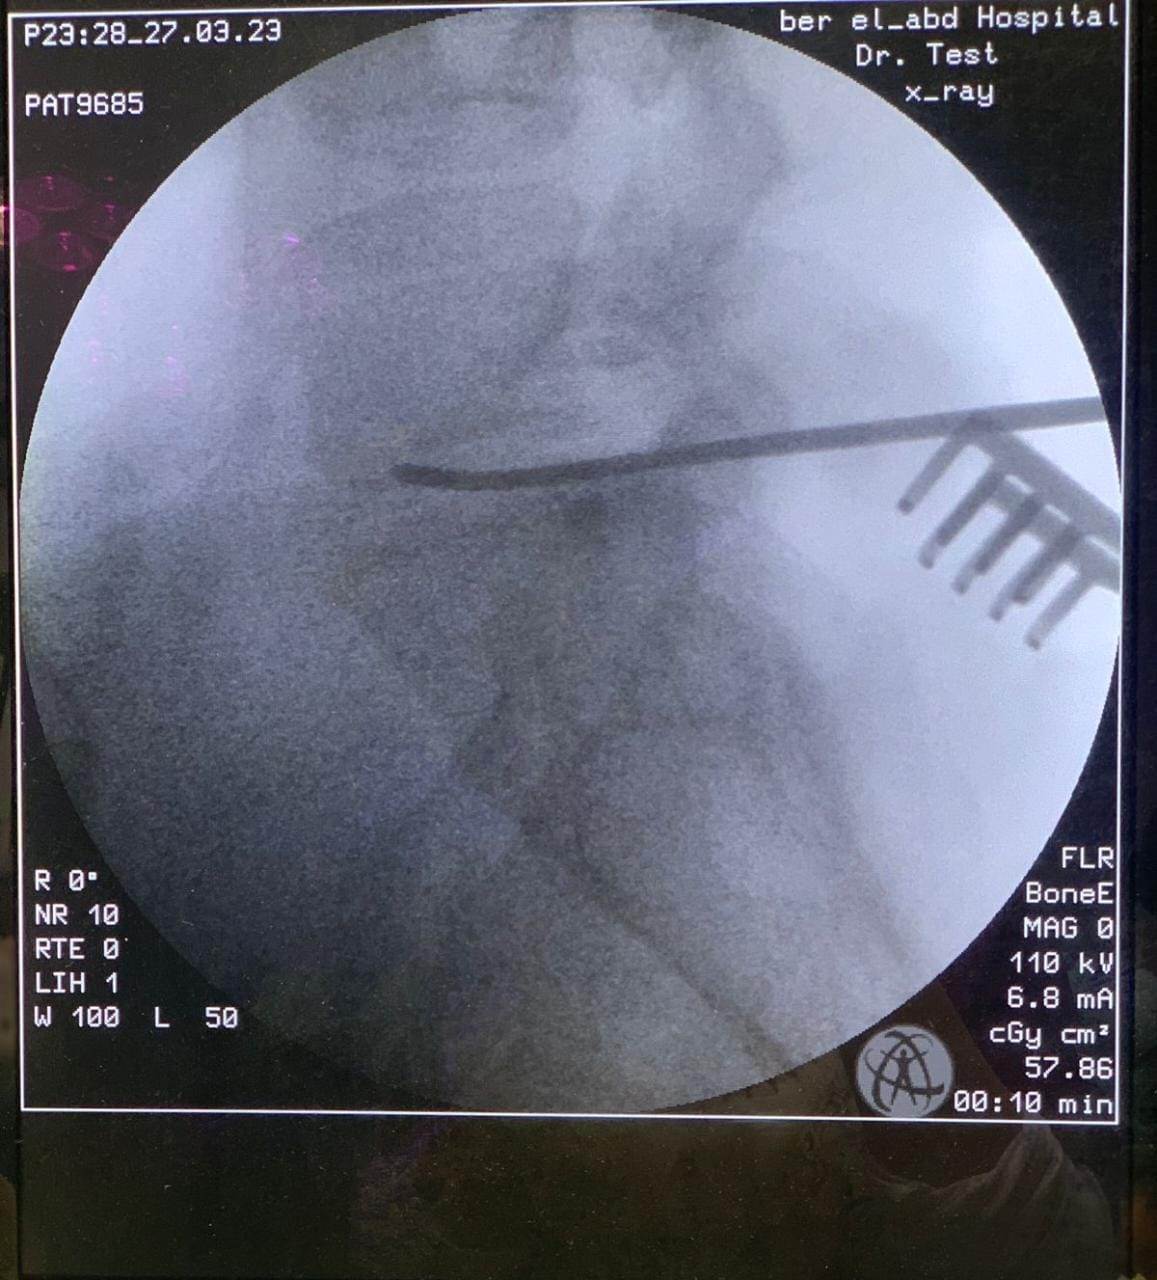

وقال الدكتور تامر حمدى أحمد مدير عام مستشفى بئر العبد التخصصى (في بيان) أنه تحت رعاية الدكتور خالد عبدالغفار وزير الصحة والدكتورة مها إبراهيم رئيس أمانة المراكز الطبية المتخصصة، والدكتور خالد الدرندلى رئيس جامعة الزقازيق والدكتور أحمد عنانى عميد كلية طب الزقازيق والدكتور محمود مصطفى طه رئيس قسم جراحة المخ والأعصاب بجامعة الزقازيق.. حيث قام الدكتور محمود محمد متولى مدرس مساعد جراحة المخ والأعصاب بجامعة الزقازيق بمساعدة الدكتور محمود الوكيل مدرس التخدير بالقصر العينى جامعة القاهرة باجراء جراحة لمريضة عمرها ٤٠عاما كانت تعانى من آلام شديدة وعرق نسا بالساق اليسرى تمنعها من المشى وممارسة حياتها اليومية بشكل طبيعى، وكانت لا تستجيب للعلاج، وأظهر الرنين المغناطيسى وجود انزلاق غضروفى ما بين الفقرات الخامسة القطنية والعجزية الأولى واختناق بجذور أعصاب الساق اليسرى، وقد تم تجهيز المريض ودخول العمليات واجراء جراحة لاستئصال الغضروف وتسليك جذور الأعصاب، وذلك من خلال جرح صغير بالظهر لا يتعدى الـ٣ سنتيمترات.

وأشار البيان الى أن هذا النوع من الجراحات فى غاية الدقة.. حيث يتم استئصال الغضروف وتسليك الأعصاب من جرح صغير بالجلد وفتحة صغيرة بالقناة الشوكية العظيمة دون التأثير على استقرار وثبات الفقرات ودون تثبيت للفقرات بشرايح ومسامير معدنية، وبواسطه تدخل محدود.